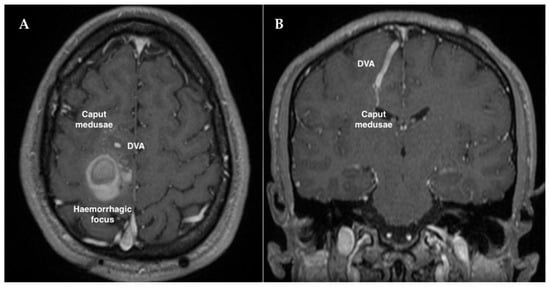

2. Case Description